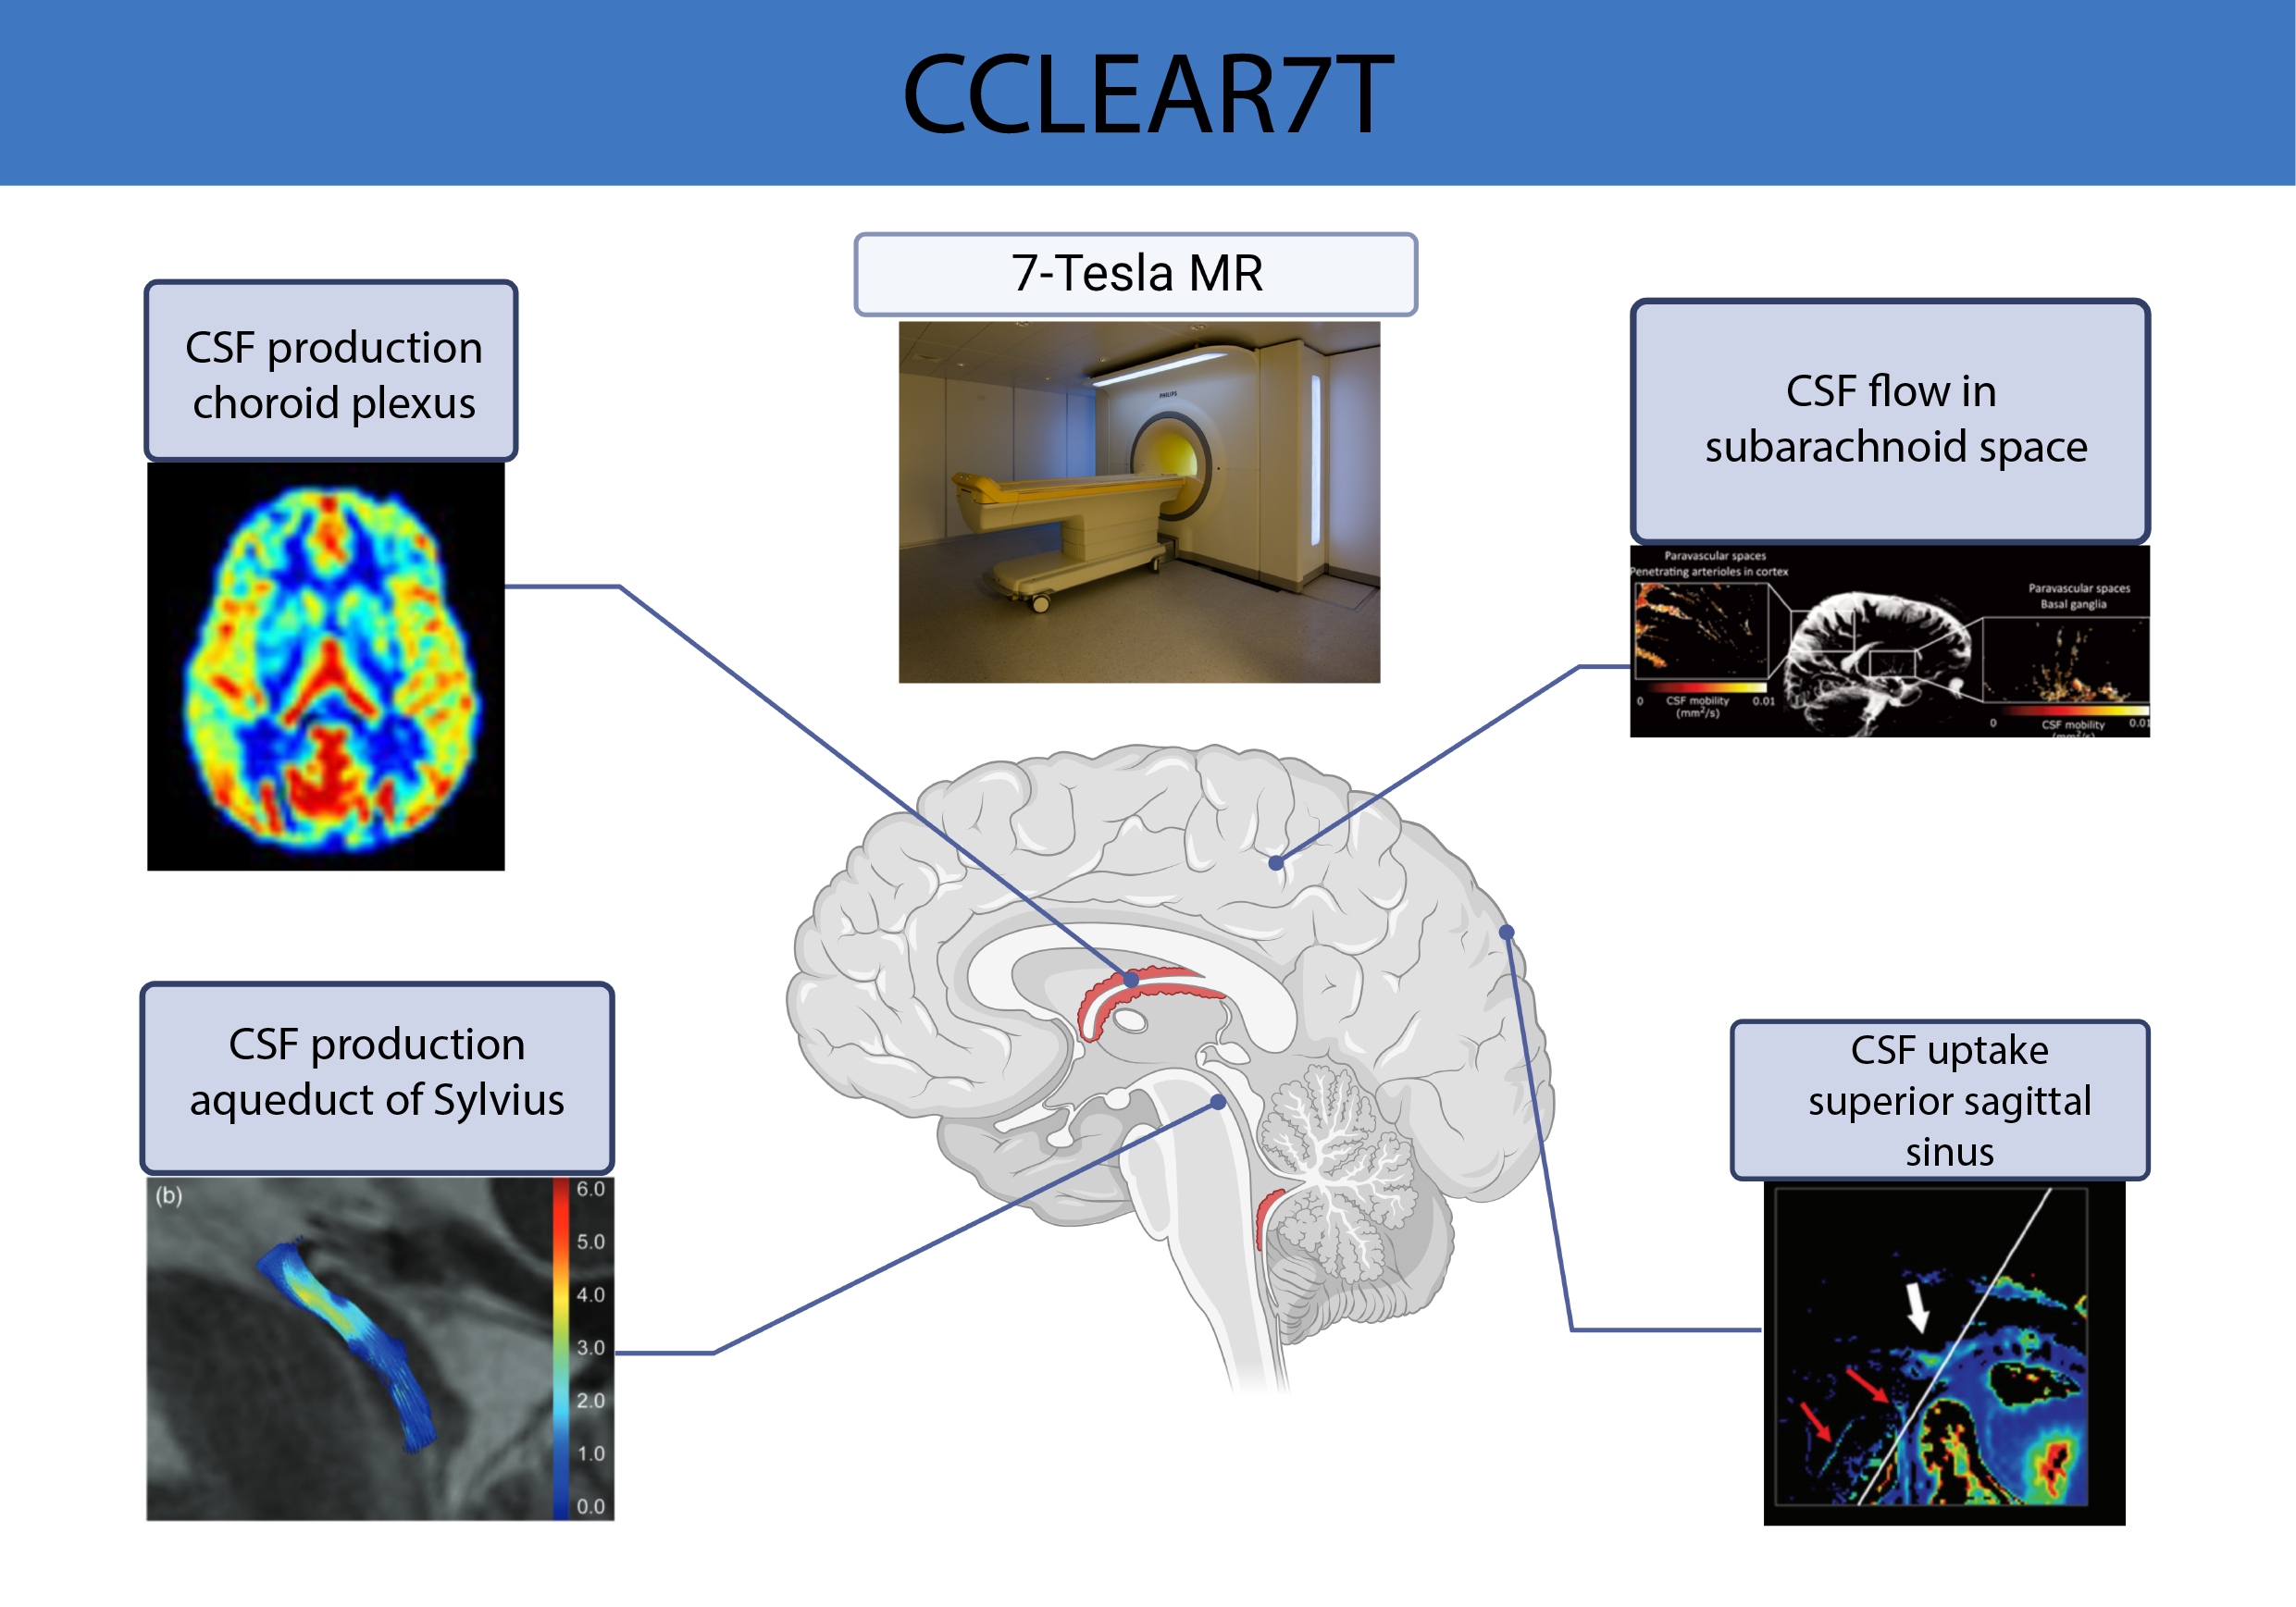

CCLEAR7T

Spontaneous intracranial hypotension (SIH) is a severe neurological disease where cerebrospinal fluid (CSF) leakage in the spine causes orthostatic headache, cognitive dysfunction, tinnitus, diplopia and, in worst cases, coma. Yet, if correctly diagnosed, it is fully treatable. Without clinical suspicion of SIH, repeated scans, misdiagnoses and fatal diagnostic delays follow. The estimated annual incidence is at least 5 per 100,000, close to other serious neurological disorders such as subarachnoid hemorrhage. Several epidemiological and pathophysiological aspects of SIH remain unexplored.

The CCLEAR7T is a collaboration between DRCMR and Danish Headache Center to use ultra-high field MRI in combination with a newly developed MRI sequence, CSF-STREAM, to measure CSF circulation as well as structural alterations in fine CSF pathways around the brain. We aim to gain unique knowledge on how the brain and CSF regulation are altered when SIH decreases intracranial pressure and whether these alterations reverse after successful treatment. Due to its mechanical nature and reversibility, SIH is a unique condition to study CSF dynamics and their influence on brain waste clearance safely in humans. The results will also inform a state-of-the-art diagnostic evaluation of SIH.

People: Kristian Nygaard Mortensen, Hartwig Siebner, Henrik Lundell, Rasmus Hansen, Sebastian Storm, Kristin Engel